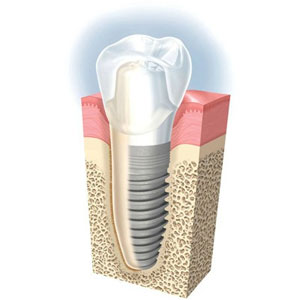

Tipos de implantes dentales, precios y dudas más frecuentes